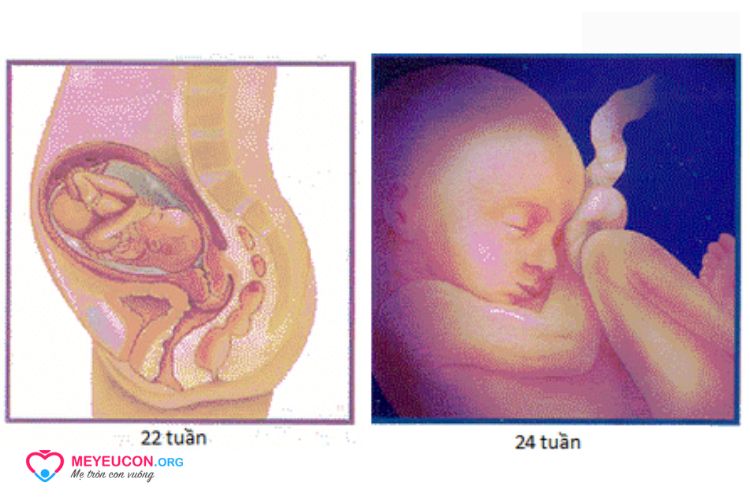

Tuần 22

Chiều dài: 21 cm; trọng lượng: 566 g

Xương của tai cứng hơn và có khả năng dẫn dao động âm. Thai nhi có thể nghe thấy âm thanh của mẹ như hơi thở, nhịp tim và giọng nói.

Các lớp đầu tiên của chất béo đang bắt đầu hình thành. Đây là sự khởi đầu cho quá trình tăng cân nhanh hơn của thai nhi.

Ở tuần này, thai nhi có 22% cơ hội sống sót khi ra bên ngoài tử cung khi được chăm sóc sơ sinh thích hợp.

Tuần 24

Chiều dài: 22 cm, trọng lượng: 907 g

Thai nhi có thể phản ứng với âm thanh từ cả bên trong và bên ngoài tử cung. Cử động phản xạ của trẻ phát triển hơn và mạnh hơn. Phổi tiếp tục phát triển. Thai nhi bây giờ đã biết thức và ngủ. Da đã chuyển sang màu đỏ, nhăn nheo và được bao phủ bởi lông mịn.

Ở tuần này, thai nhi có 35% cơ hội sống sót khi ra bên ngoài tử cung khi được chăm sóc sơ sinh thích hợp.